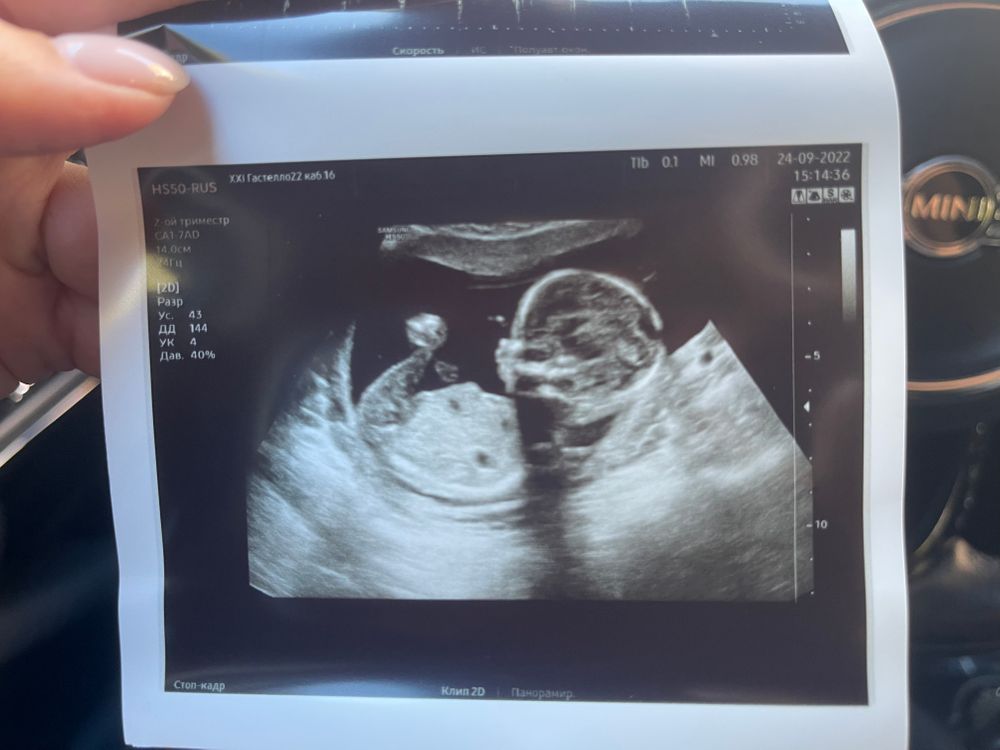

И заодно сохраню фото пузико на 17ой неделе)